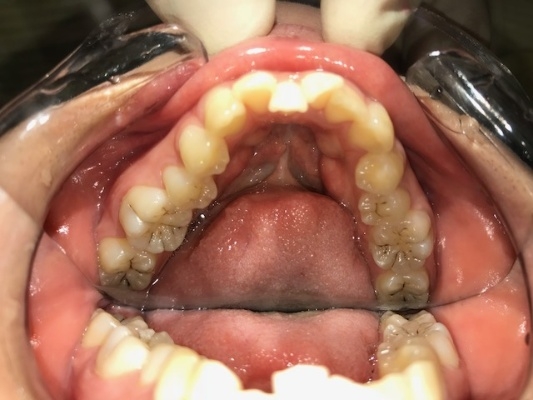

下顎